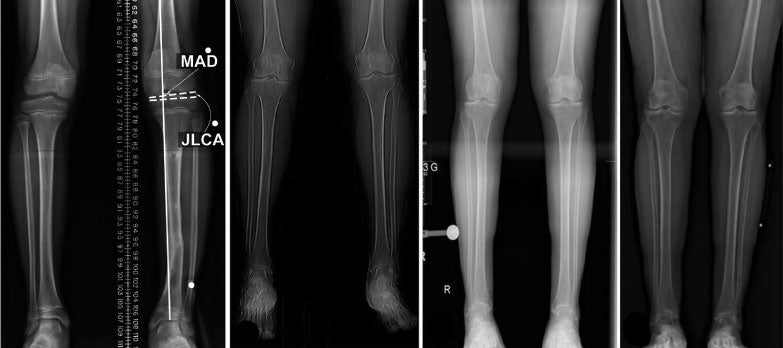

Different providers have various methods for determining limb length. It’s common for legs to be evaluated with tape measures while the patient is standing or lying down. Providers will also frequently determine leg length by visually assessing posture. Unfortunately, these methods have been proven unsuccessful and unscientific at accurately determining leg length. In addition, they do not establish if the difference is due to a structural or functional discrepancy. Dr. McClanahan recommends evaluation of limb length via a Scanogram, or a standing X-ray. These tests involve radiographic images that measure the distance from the pelvis through the talus, a key ankle bone. This method helps to accurately determine overall limb length as well as where the limb is short.